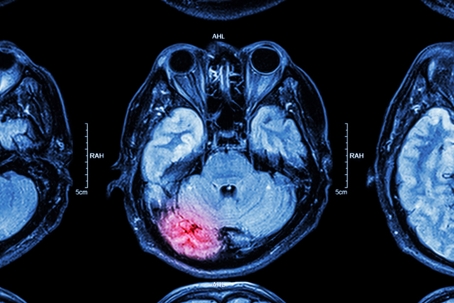

TBI Xray

Concussions are a type of traumatic brain injury (TBI) that can disrupt normal brain function. Though they might initially be considered mild, or non-life-threatening their effects can be long-lasting and severe.

Concussions are often caused by acceleration or deceleration forces occurring secondary to a direct blow to the head. This causes a transient altered mental status, which can range from confusion to loss of consciousness. Nearly every accident type, from slip-and-falls to trucking accidents, can cause concussions and impact the most critical organ in the body – the brain.

Concussions can cause headaches, dizziness, confusion, memory loss, and even changes in mood and behavior. In severe cases, multiple concussions can lead to chronic traumatic encephalopathy (CTE), a degenerative brain condition.